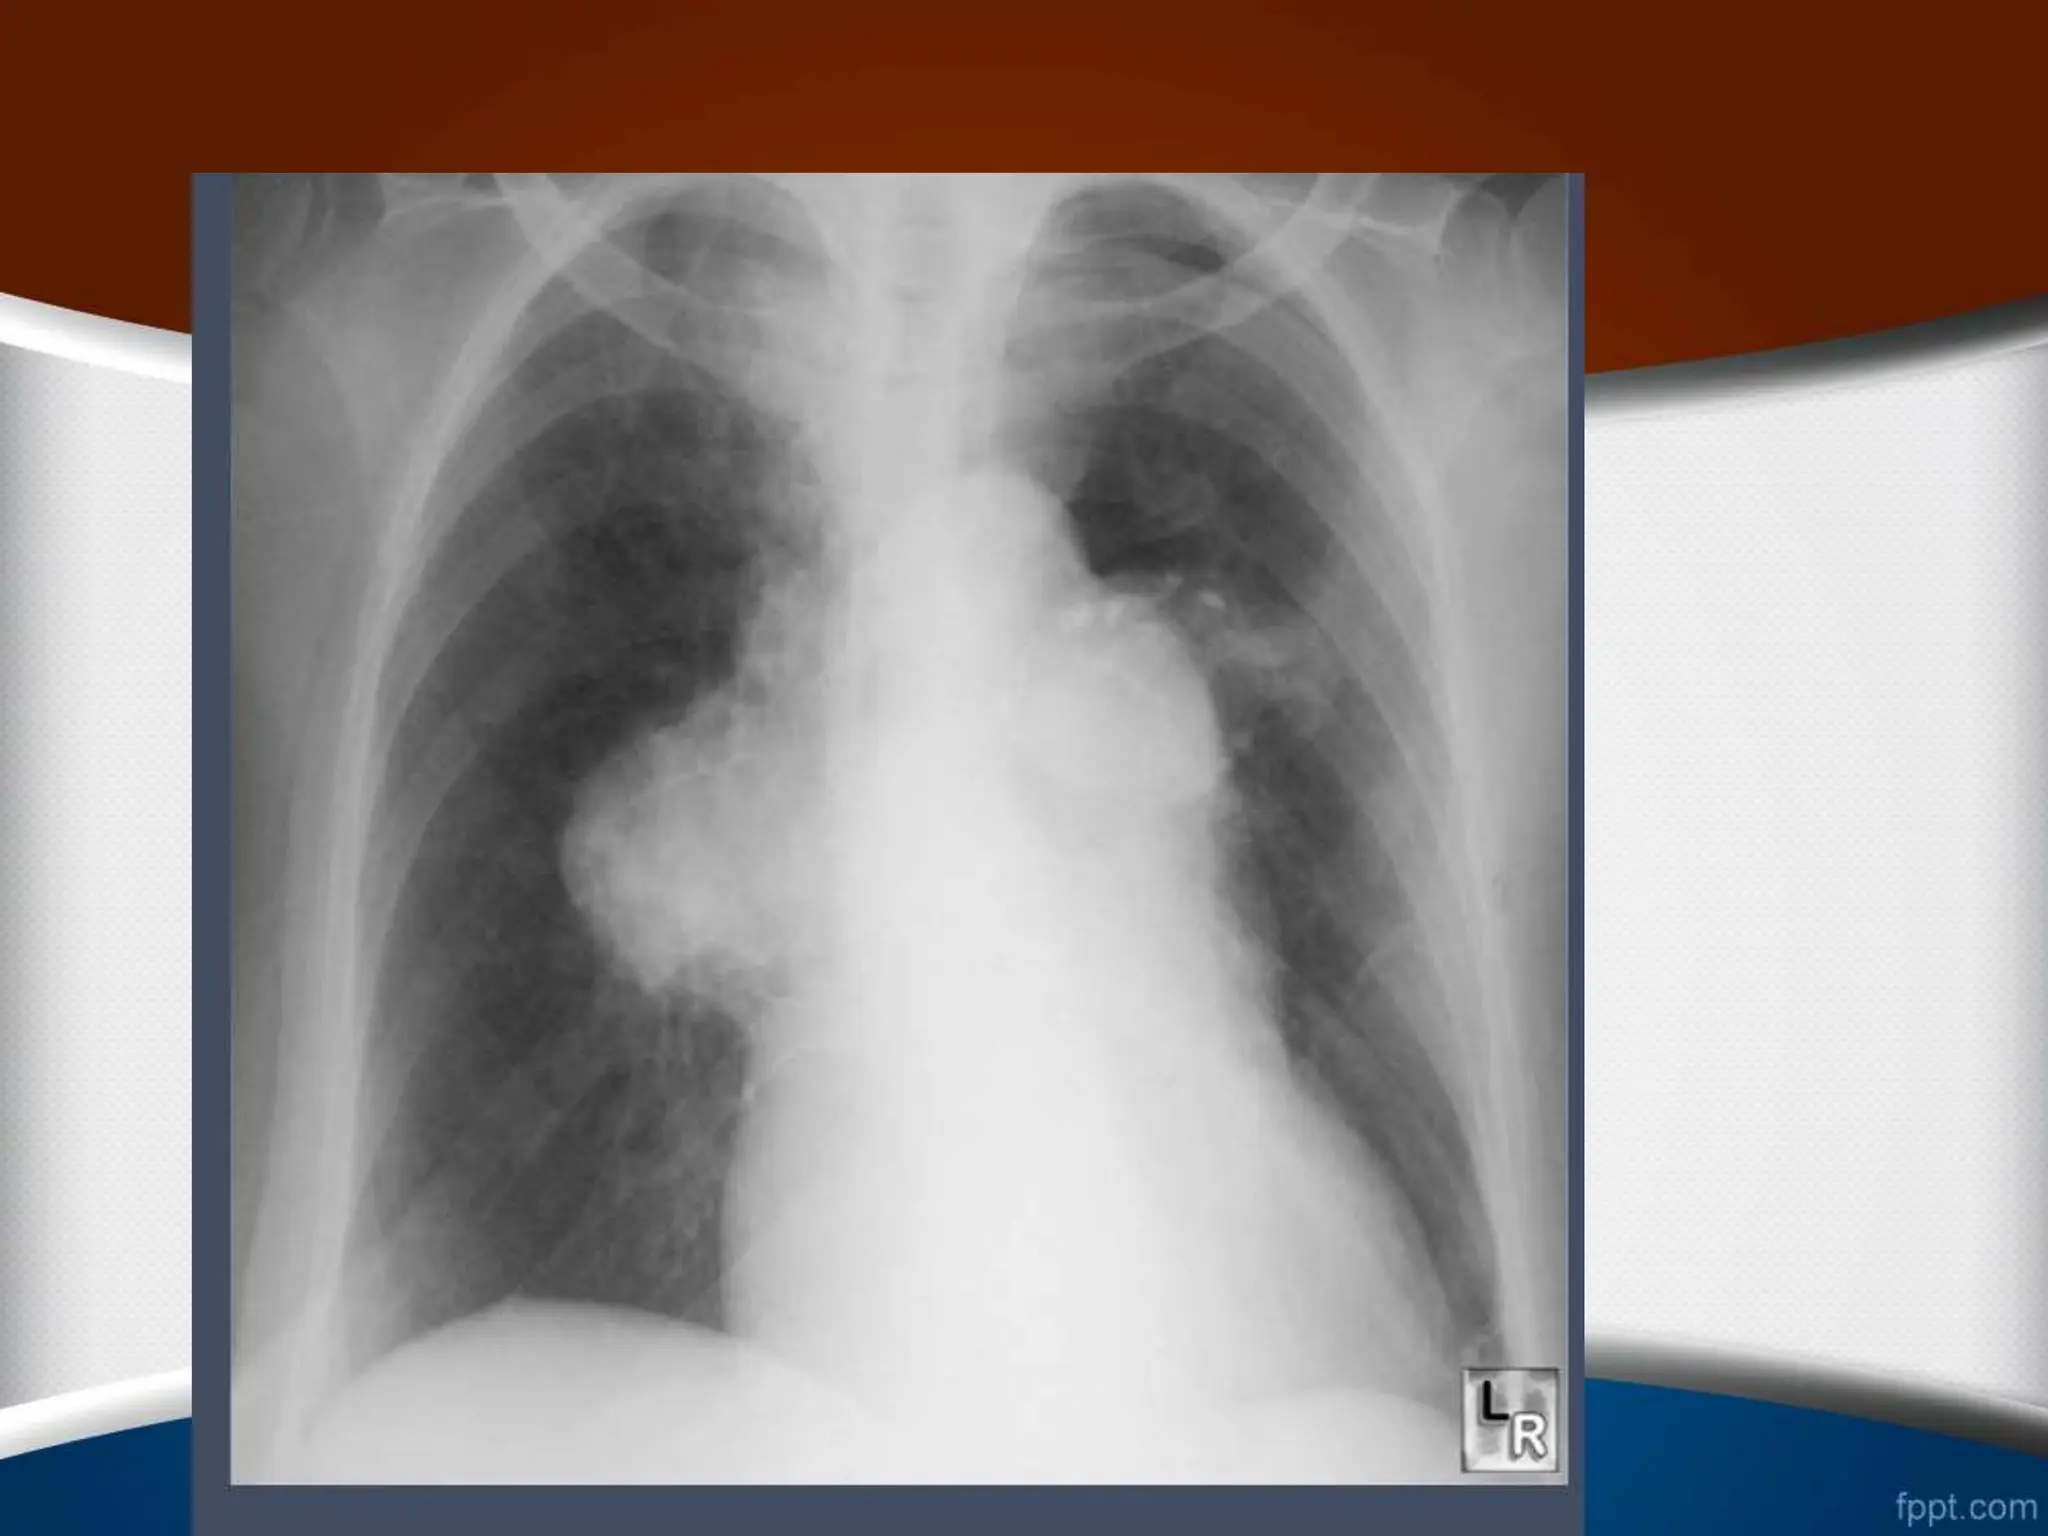

‫چپ‬ ‫بطن‬ ‫بزرگی‬

•

‫اکسنتریک‬ ‫هیپرتروفی‬

‫کانسنتریک‬ ‫هیپرتروفی‬

-

‫شکل‬ ‫کروی‬ ‫بزرگی‬

‫راست‬ ‫بطن‬ ‫بزرگی‬

‫گرافی‬ ‫در‬ ‫هم‬ ‫مورد‬ ‫این‬ ‫در‬

PA

‫نوک‬ ‫شدن‬ ‫گرد‬ ‫سینه‬ ‫قفسه‬

‫دی‬ ‫دیافراگم‬ ‫باالی‬ ‫طرف‬ ‫به‬ ‫آن‬ ‫جایی‬ ‫جابه‬ ‫با‬ ‫همراه‬ ‫قلب‬

‫ده‬

‫شود‬ ‫می‬

.

ً‫ال‬‫معمو‬ ‫راست‬ ‫بطن‬ ‫شدید‬ ‫بزرگی‬ ‫در‬

CTR

‫یافته‬ ‫افزایش‬

‫است‬